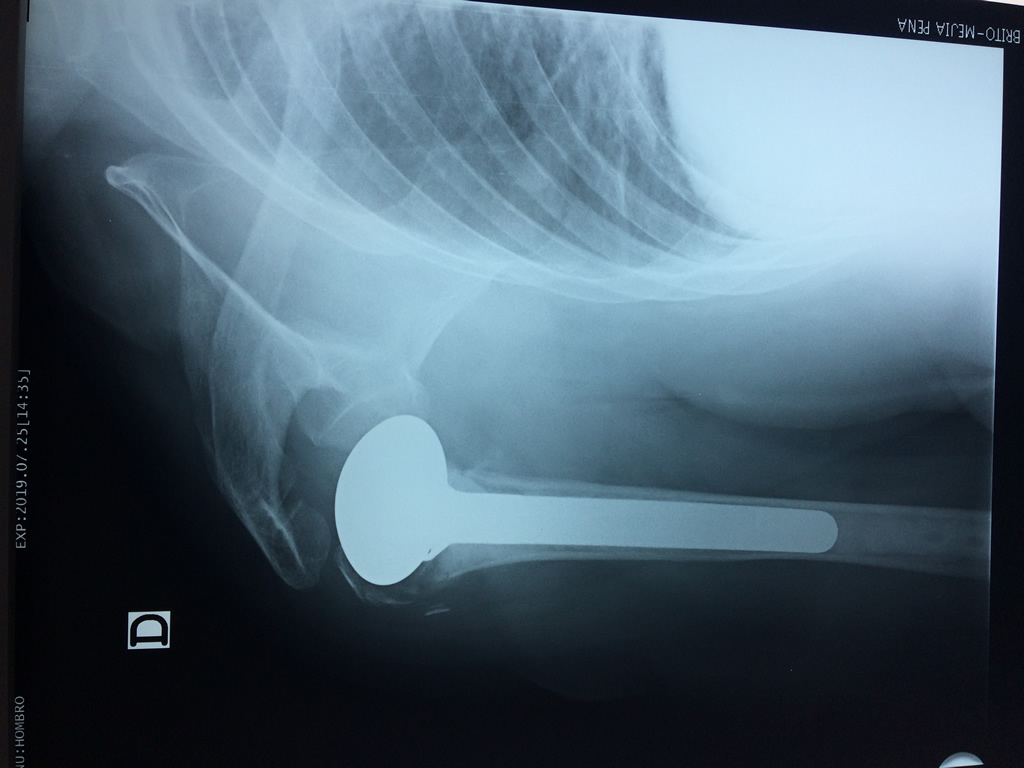

Cirugías de Húmero - Hombros

La principal articulación del hombro es la que une la cabeza del húmero con la escápula, recibe el nombre de articulación escapulohumeral y presenta dos superficies articulares, una de ellas corresponde a la cabeza del humero que tiene forma semiesférica y la otra es la cavidad glenoidea de la escápula, estas superficies están recubiertos por cartílago que permiten un movimiento suave e indoloro.